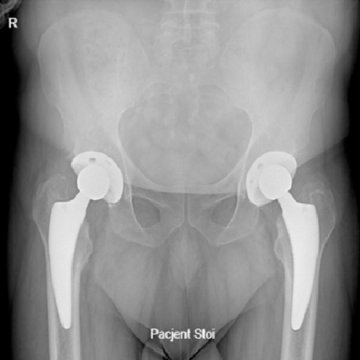

Endoproteza stawu biodrowego

Endoprotezoplastyka stawu biodrowego to skuteczna metoda leczenia choroby zwyrodnieniowej, jałowej martwicy głowy kości udowej, dysplazji oraz innych zmian zwyrodnieniowo-destrukcyjnych stawu jak i złamań szyjki kości udowej. Zabieg polega na usunięciu zniszczonych struktur stawu i zastąpieniu ich odpowiednio dobranym implantem, przywracającym funkcję, ruchomość i komfort życia.

Zabieg wykonuję z użyciem wysokiej jakości, nowoczesnych implantów dobieranych indywidualnie do budowy anatomicznej i potrzeb pacjenta. Całość leczenia opiera się na zasadach tzw. szybkiej ścieżki (fast-track), co oznacza także odpowiednio zaplanowaną rehabilitację i stały nadzór pooperacyjny. Dzięki takiemu podejściu, endoprotezoplastyka biodra w moim wykonaniu stanowi skuteczną i bezpieczną metodę leczenia zwyrodnienia stawu biodrowego – szczególnie dla pacjentów oczekujących szybkiego powrotu do sprawności.